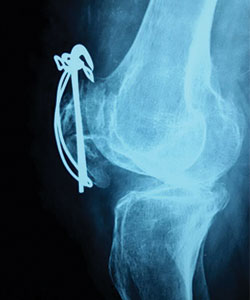

Case 7: Total Knee Replacement

54 years female was suffering from both knee pain for last 4-5 years. She had bilateral advanced osteoarthritis knee.

Patient underwent knee replacement surgery in two stages. 1st right knee was replaced after 8 months left knee was replaced.

X-RAY 1

knee advanced stage of osteoarthritis

X-RAY 2

post op xray after knee replacement

X-RAY 3

xray left knee lateral view after knee replacement